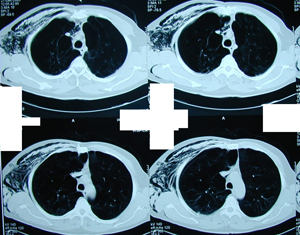

Εικόνα 4

Οπισθιο–πρόσθια ακτινογραφία θώρακος μετά από περιορισμένη θωρακοτομή.

Παρατηρείται πλήρης έκπτυξη του πνεύμονος μετά από αφαίρεση των κύστεων, την αφαίρεση του τοιχωματικού υπεζωκότα και την συρραφή του πνεύμονα στο σημείο της διαφυγής του αέρα.